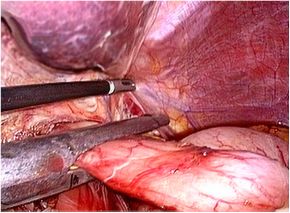

腹腔鏡下胃切除術の実際

全身麻酔下で手術を行います。まず腹腔内(腹腔:お腹の壁と臓器との間の空間)に炭酸

ガスを入れて膨らませ、お臍からカメラ(腹腔鏡)を挿入します。同時に手術操作に用い

る器具(鉗子など)を挿入するための5〜10mmの小さな穴を左右に4カ所開けます。そ

して腹腔鏡で撮ったお腹の中の様子をモニターに映し出して、胃切除や周囲のリンパ節

の切除を行います。開腹手術では見えにくかった細い血管や神経まで見えて繊細な手術

操作が可能です。

胃切除、切除後の再建を体外で行う場合は、開腹手術ほど大きな創にはなりませんが、

どうしても5〜7cmの切開創(傷)が必要となります。(腹腔鏡補助下胃切除術)

現在当院では、胃切除・切除後の再建を体内で行うため、切除した胃を取り出すための

切開創(傷)はお臍の上約2〜3cmで十分であり、腹腔鏡補助下での手術よりも更に小さ

な創で手術を完遂する事が可能となります。(完全腹腔鏡下胃切除術)

当院での腹腔鏡下胃切除術は「完全腹腔鏡下胃切除術」を主に行っています。